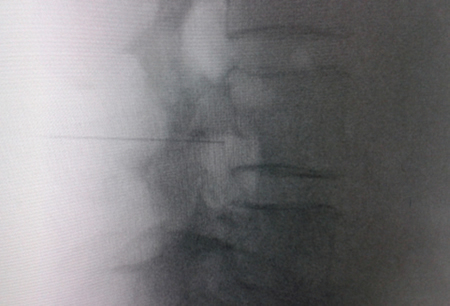

El acceso por vía transforaminal es el más utilizado (4). Se coloca al paciente en decúbito prono con una almohada a nivel abdominal para revertir la lordosis fisiológica. Las agujas o cánulas de radiofrecuencia que utilizamos con más frecuencia son de diámetro 20 o 22 G de 98 mm de largo con punta activa de 0,5 o 1 cm. Después de la asepsia con clorhexidina alcohólica y la colocación de campos estériles, se realizan enfoques radiológicos en incidencia anteroposterior, oblicuo y lateral. En incidencia anteroposterior y moviendo el arco en dirección cráneo caudal se borra el doble arco del borde inferior vertebral. En incidencia oblicua entre 20 y 30 grados ipsilateral al GRD a tratar, se visualizará la clásica imagen descrita como de “Scotty Dog”, que es resultado de acercar el macizo facetario y la apófisis espinosa al lado contralateral. El punto de entrada será entonces inmediatamente debajo del pedículo. Previa anestesia local con lidocaína al 1 %, la aguja se introducirá siguiendo una visión túnel y no se avanzará más allá de la mitad del pedículo en esta proyección con la finalidad de prevenir la lesión neural. En proyección lateral, se introducirá en el techo del neuroforamen

(Figuras 1 y 2) pero la localización final será determinada por la estimulación nerviosa sensitivo-motora. La estimulación sensitiva consiste en provocar parestesia o dolor en el territorio afectado con una estimulación entre 0,3-0,6 v. Durante la estimulación motora se pueden provocar fasciculaciones en el territorio afectado con un voltaje del doble al necesario para provocar las parestesias. Si se desea realizar una denervación intraganglionar, promulgada por algunos autores, la estimulación tanto sensorial como motora será positiva a menos de 0,3 v. Por tratarse de un procedimiento más doloroso, se aconseja administrar anestésicos locales después del estímulo doloroso y antes de realizar el tratamiento. La impedancia deberá mantenerse por debajo de 450 ohms, lo que se consigue infundiendo solución salina previa a la RF (4). La utilización de contraste constituye una buena práctica, ya que descarta la posición intravascular e intratecal de la cánula de radiofrecuencia.

Fig. 2. Imagen radiológica anteroposterior de una cánula de radiofrecuencia posicionada en neuroforamen L4-L5, en el llamado triángulo de seguridad, después de la inyección de contraste. Se observa un engrosamiento del radiculograma a nivel del techo del neuroforamen, que podría corresponder al ganglio de la raíz dorsal de L4